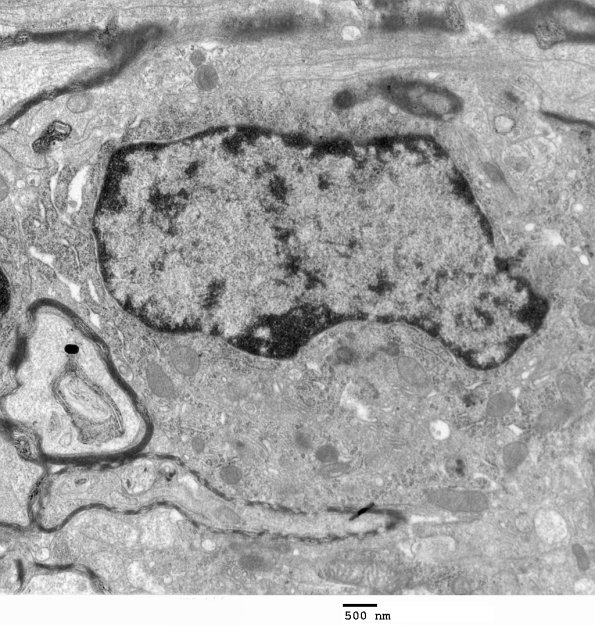

An oligodendroglial cell exhibiting a dense, dark cytoplasm, a round/oval nucleus with clumped chromatin, abundant ribosomes and endoplasmic reticulum (ER) and lack of glycogen. (electron micrograph)